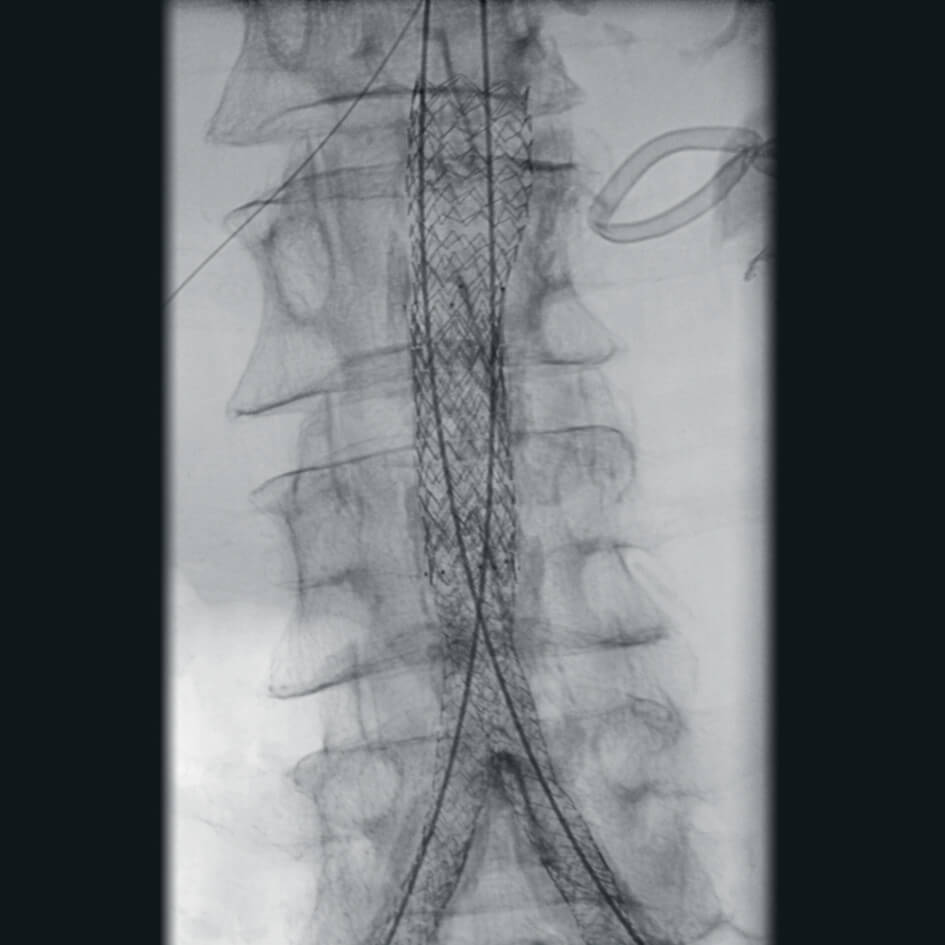

Полное отсутствие искажений снимков в сочетании с высоким динамическим диапазоном широко востребованы как при сложных операциях в нейрохирургии, сосудистой хирургии, инвазивной радиологии, так и в гибридных областях применения, а также в ортопедии, травматологии. В сосудистой хирургии особенно важны высокий динамический диапазон и пространственное разрешение, обеспечивающие детальную визуализацию даже мельчайших сосудов. Специализированное программное обеспечение SmartVascular позволяет проводить настройку системы для васкулярных операций и сосудистой хирургии.

- программный пакет для сосудистой хирургии,

- субтракционная ангиография с применением СО2.